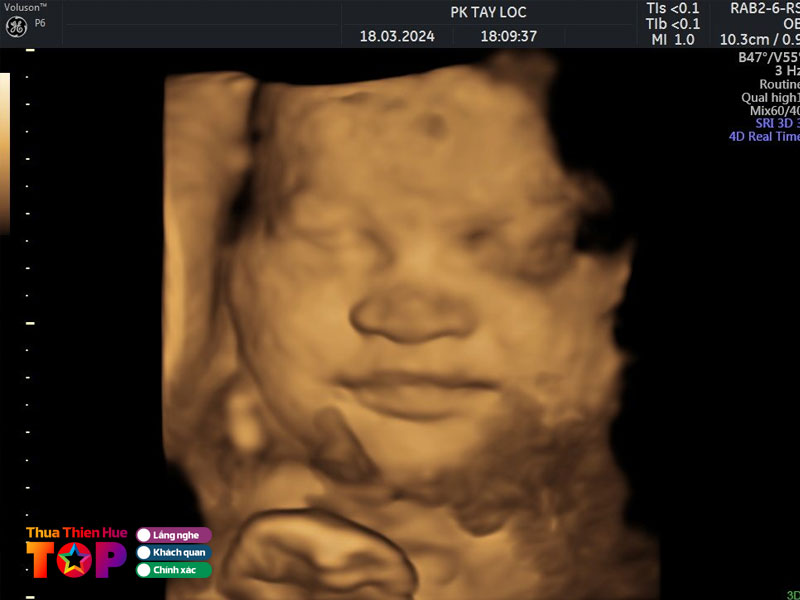

Phòng khám Tây Lộc

So với các phòng khám khác trên địa bàn thì Phòng khám Tây Lộc là một trong những phòng khám thai ở Huế có chất lượng dịch vụ tốt. Phòng khám sở hữu đội ngũ y bác sĩ trình độ cao, lương y như từ mẫu. Đặc biệt là họ nhiệt huyết thăm khám và chữa trị bệnh cho thai phụ.

Phòng khám lấy khách hàng làm trung tâm và lợi ích của khách lên hàng đầu. Chính vì vậy mà đơn vị đã không ngừng nỗ lực đào tạo đội ngũ y bác sĩ. Đồng thời đầu tư máy móc, thiết bị tiên tiến nhằm phục vụ tốt nhu cầu khám, chẩn đoán một cách chính xác và nhanh chóng nhất.

Thông tin liên hệ:

Địa chỉ: 31 Lê Đại Hành, Tây Lộc, TP. Huế

Điện thoại: 0914 457 689 & 0823 876 762

Fanpage: Phòng khám Siêu âm Tây Lộc